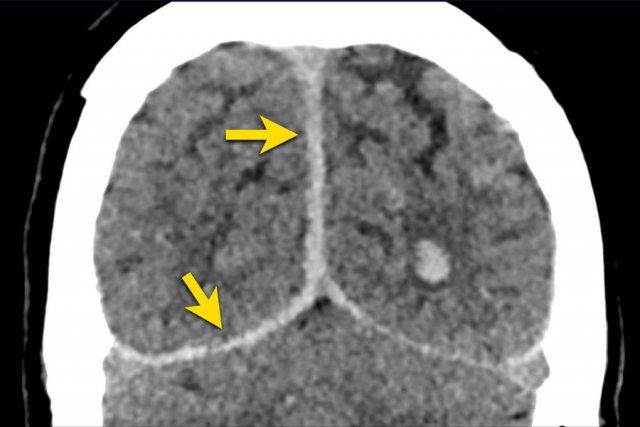

Chấn thương năng lượng cao với lực gia tốc-giảm tốc, đặc biệt là gia tốc xoay, có thể gây kéo căng và biến dạng mô não, dẫn đến tổn thương sợi trục lan tỏa (DAI).

CT có độ nhạy thấp trong phát hiện DAI.

Trong chấn thương sọ não kín không có xuất huyết dưới nhện do chấn thương hoặc xuất huyết não thất, DAI ít có khả năng xảy ra.

Bệnh nhân nam 46 tuổi bị chấn thương năng lượng cao khi đi xe máy.

Điểm EMV ban đầu là 2-5-3 và đồng tử hai bên giãn không phản xạ ánh sáng.

Hình ảnh CT

- Xuất huyết dạng chấm ở cả hai thùy trán.

- Gãy xương Le Fort II hai bên.